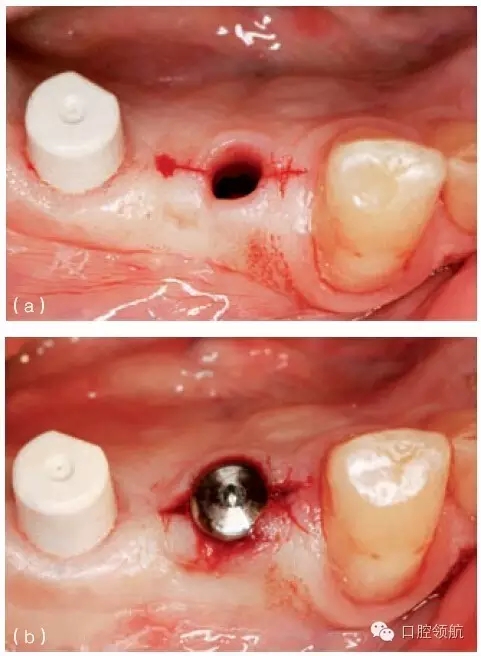

另外一個方面,深的袖口將妨礙修復體完全就位(圖9.26)。通??梢酝ㄟ^放射學檢查,確認修復部件的就位情況,包括種植體與基臺的連接部分。即使是內(nèi)連接,轉(zhuǎn)移體或者其他修復部件也會因深袖口而不能就位。以下技術可以用于解決這些問題:可以在局部麻醉下,插入喇叭狀或者外展的基臺,以非手術的方式擴大袖口(圖9.27 a,b),然后再通過放射學檢查確定部件的完全就位。組織會受壓發(fā)白,15分鐘后,軟組織將會擴張,以允許理想修復部件的就位,這樣治療將得以繼續(xù)。有時,需要在鄰面做兩個小切口,以緩解袖口軟組織張力(圖9.28 a,b)。通常不需要縫合。一旦袖口組織塑形完成,可運用最佳塑形的臨時(圖9.29)或最終部件(圖9.30),來維持理想的軟組織外形。

圖9.27 (a)種植體植入時,使用窄頸的愈合基臺。(b)二期暴露時,可以采用寬頸愈合基臺,拓展袖口以適應修復的需要。

圖9.28 (a)做鄰面切口,使軟組織易于擴張,以適應外展的愈合基臺。(b)寬頸愈合帽就位,阻力很小。